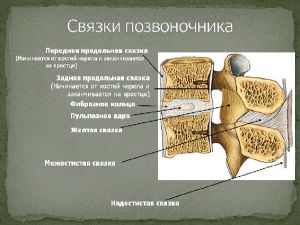

Немного анатомии. Позвоночный канал спереди образован телами позвонков и межпозвонковыми дисками, сзади дужками позвонков, между которыми находится плотная желтая связка, с боков – фасеточными суставами. В позвоночном канале находится спинной мозг с выходящими из него спинномозговыми корешками, окруженный соединительнотканной оболочкой: т.н. твердой мозговой оболочкой образующей дуральный мешок. (Рис.3,4,5).

Рис. 5. Связки позвоночника (пояснично-двигательный сегмент). |